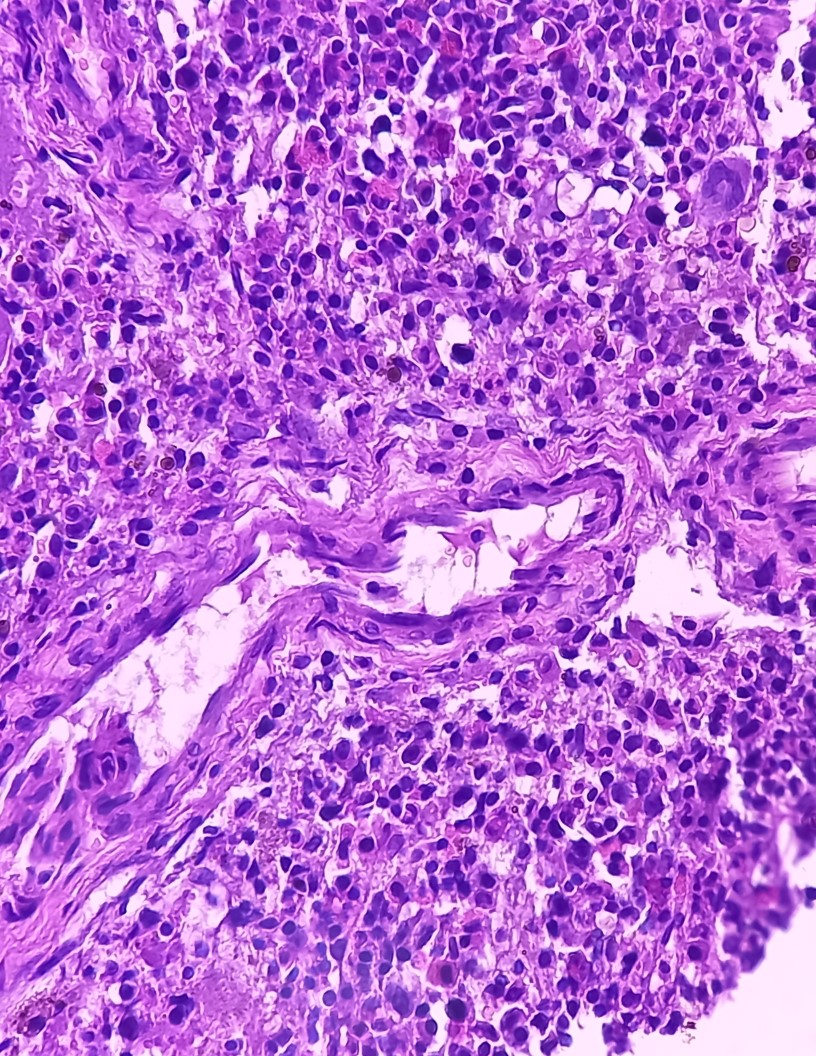

Non-Hodgkin Lymphoma (NHL) is a type of hematologic malignancy, accounting for approximately 45% of all newly diagnosed lymphomas. The disease manifests through the abnormal proliferation of lymphocytes, leading to the formation of tumors in lymph nodes and other organs. The NHL therapeutics market is witnessing significant advancements due to the introduction of novel treatment modalities, including chemotherapy, targeted therapies, and immunotherapy. Chemotherapy remains a cornerstone of NHL treatment, with alkylating agents, anthracyclines, and corticosteroids being the most commonly used drugs. However, the side effects associated with chemotherapy, such as myelosuppression and neurotoxicity, necessitate the exploration of alternative therapeutic approaches.

Non-Hodgkin Lymphoma (NHL) is a type of hematologic malignancy characterized by the uncontrolled proliferation of abnormal lymphocytes. The therapeutic landscape for NHL is diverse and includes chemotherapy, targeted therapies, and immunotherapy. Chemotherapy remains a mainstay treatment for many NHL subtypes, while targeted therapies and immunotherapies are increasingly being used to address genetic mutations and molecular subtypes. Signaling pathways and genetic abnormalities play a crucial role in the development and progression of NHL. Diagnostic techniques, such as molecular testing and imaging, aid in identifying the specific subtypes and guiding treatment decisions. Precision medicine and healthcare policies are driving the development of new NHL drugs, including CAR T-cell therapies like C-CAR and Lisocabtagene Maraleucel, and monoclonal antibodies like Rituximab.

Pharmaceutical companies and research institutions are at the forefront of advancing NHL therapeutics, with ongoing research focusing on immune checkpoint inhibitors and novel targeted therapies. Radiation therapy, including intensity-modulated radiation therapy and proton therapy, also plays a role in the treatment of localized NHL. Healthcare systems and providers offer various treatment options, including hospital pharmacies and online pharmacies, for administering NHL drugs. The Oncology Journal and other publications provide valuable insights into the latest research and advancements in NHL therapeutics. Axicabtagene Ciloleucel and other emerging NHL drugs offer hope for patients, although toxicities associated with these therapies remain a concern. B cell lymphomas and T cell lymphomas are the two main categories of NHL, with B cells being the most common type. Understanding the unique characteristics of each subtype is essential for effective treatment and improving patient outcomes.